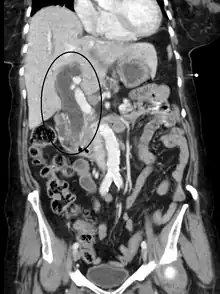

Biliary tract dilation due to obstruction as seen on CT scan (sagittal plane)

Biliary tract dilation due to obstruction as seen on CT scan (axial plane)

Medical imaging such as ultrasound, CT scan, and HIDA scans are useful for detecting bile duct blockage.[12]